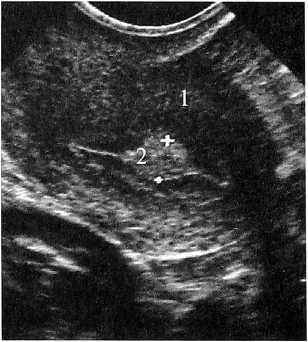

Рис. 1. Больная К. 36 лет. 11 день МЦ.

ЛУГ в эндометрии в середине полости матки. Продольное ТВ-сканирование. 1 — матка, 2 — М-эхо с ЛУГ (УЗ картина напоминает одиночный полип эндометрия)

Контуры ЛУГ были ровные, четкие, как бы подчеркнутые, каждое из образований было окружено тонкой равномерной по толщине гиперэхогенной полоской, которая «как бы» огибала его с двух сторон и плавно переходила в неизмененный центральный отдел эндометрия — срединную гиперэхогенную линию (см. рис. 1, 2).